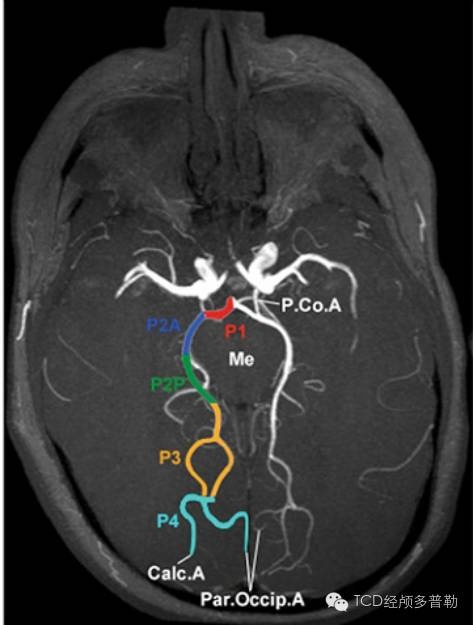

01大脑后动脉的解剖分段大脑后动脉可以分为4段:p1交通前段,p2环池段

图-6大脑后动脉的分段i段:自大脑后动脉起点至连接后交通动脉处;Ⅱ段